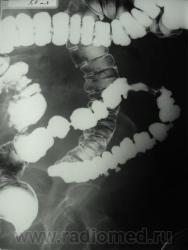

ирригоскопия

женщина 1934 г.р. жалоб не предъявляет, в анамнезе анемия.

cr сигмы

Да, похоже на неолазию сигмы. но всё же для верификации нужна гистология (колоноскопия с биопсией).

Скорей всего так, но переменчива картина. Хотелось бы узнать продолжение.

женщину только отправили на колоноскопию, как приедит результат напишу